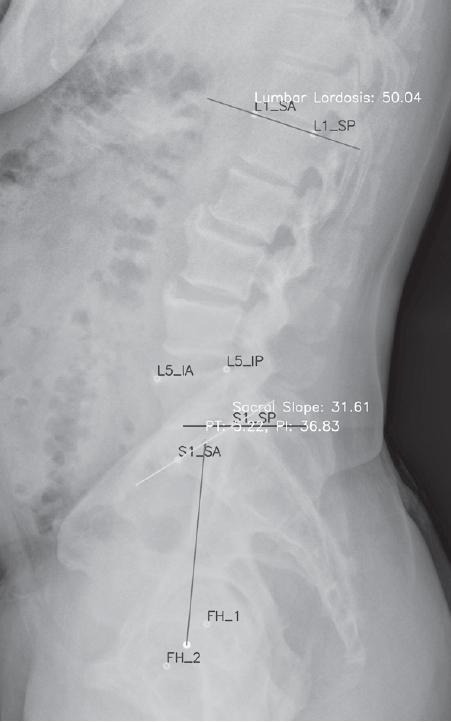

A total of 904 patients were included in the analysis. A representative image of lumbar lordosis measured by the AI-based automated model is shown in Fig. 1. The age distribution of the study population is presented in Table 1. The 60–69-year group comprised the largest proportion, with 203 patients (22.5%), followed by the 10–19-year group with 169 patients (18.7%). In contrast, the 20–29-year group had the smallest representation, with 26 patients (2.9%). Overall, a substantial number of patients were concentrated in the older adult (60–79 years). Females (548 patients, 60.6%) outnumbered males (356 patients, 39.4%).

Fig. 1.

A representative image measured by the AI-based automated measurement model. In addition to lumbar lordosis, spinopelvic parameters such as sacral slope, pelvic tilt, and pelvic incidence can also be measured.